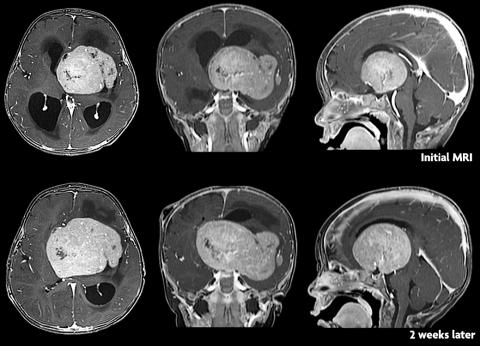

四周:

一行:较初的轴位、冠状位和矢状位增强T1WI显示鞍上肿块增大。

二行:2周后随访轴位、冠状位和矢状位增强T1WI显示大肿块增大。